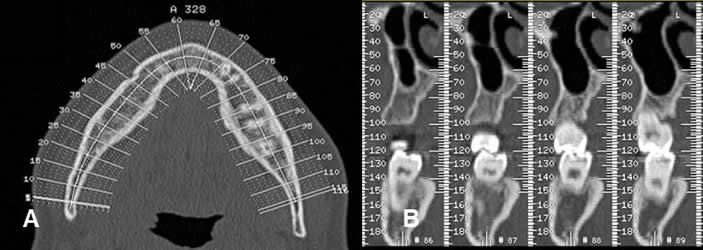

Fig 21. Dentascan.

Reconstrucción panorámica, obtenida de un dentascan. Ausencia de varias piezas dentales.

Fig 22. Dentascan.

A: Topograma y B: Reconstrucciones ortogonales. Cortes obtenidos con el programa dentascan, que permite caracterizar la región de interés.